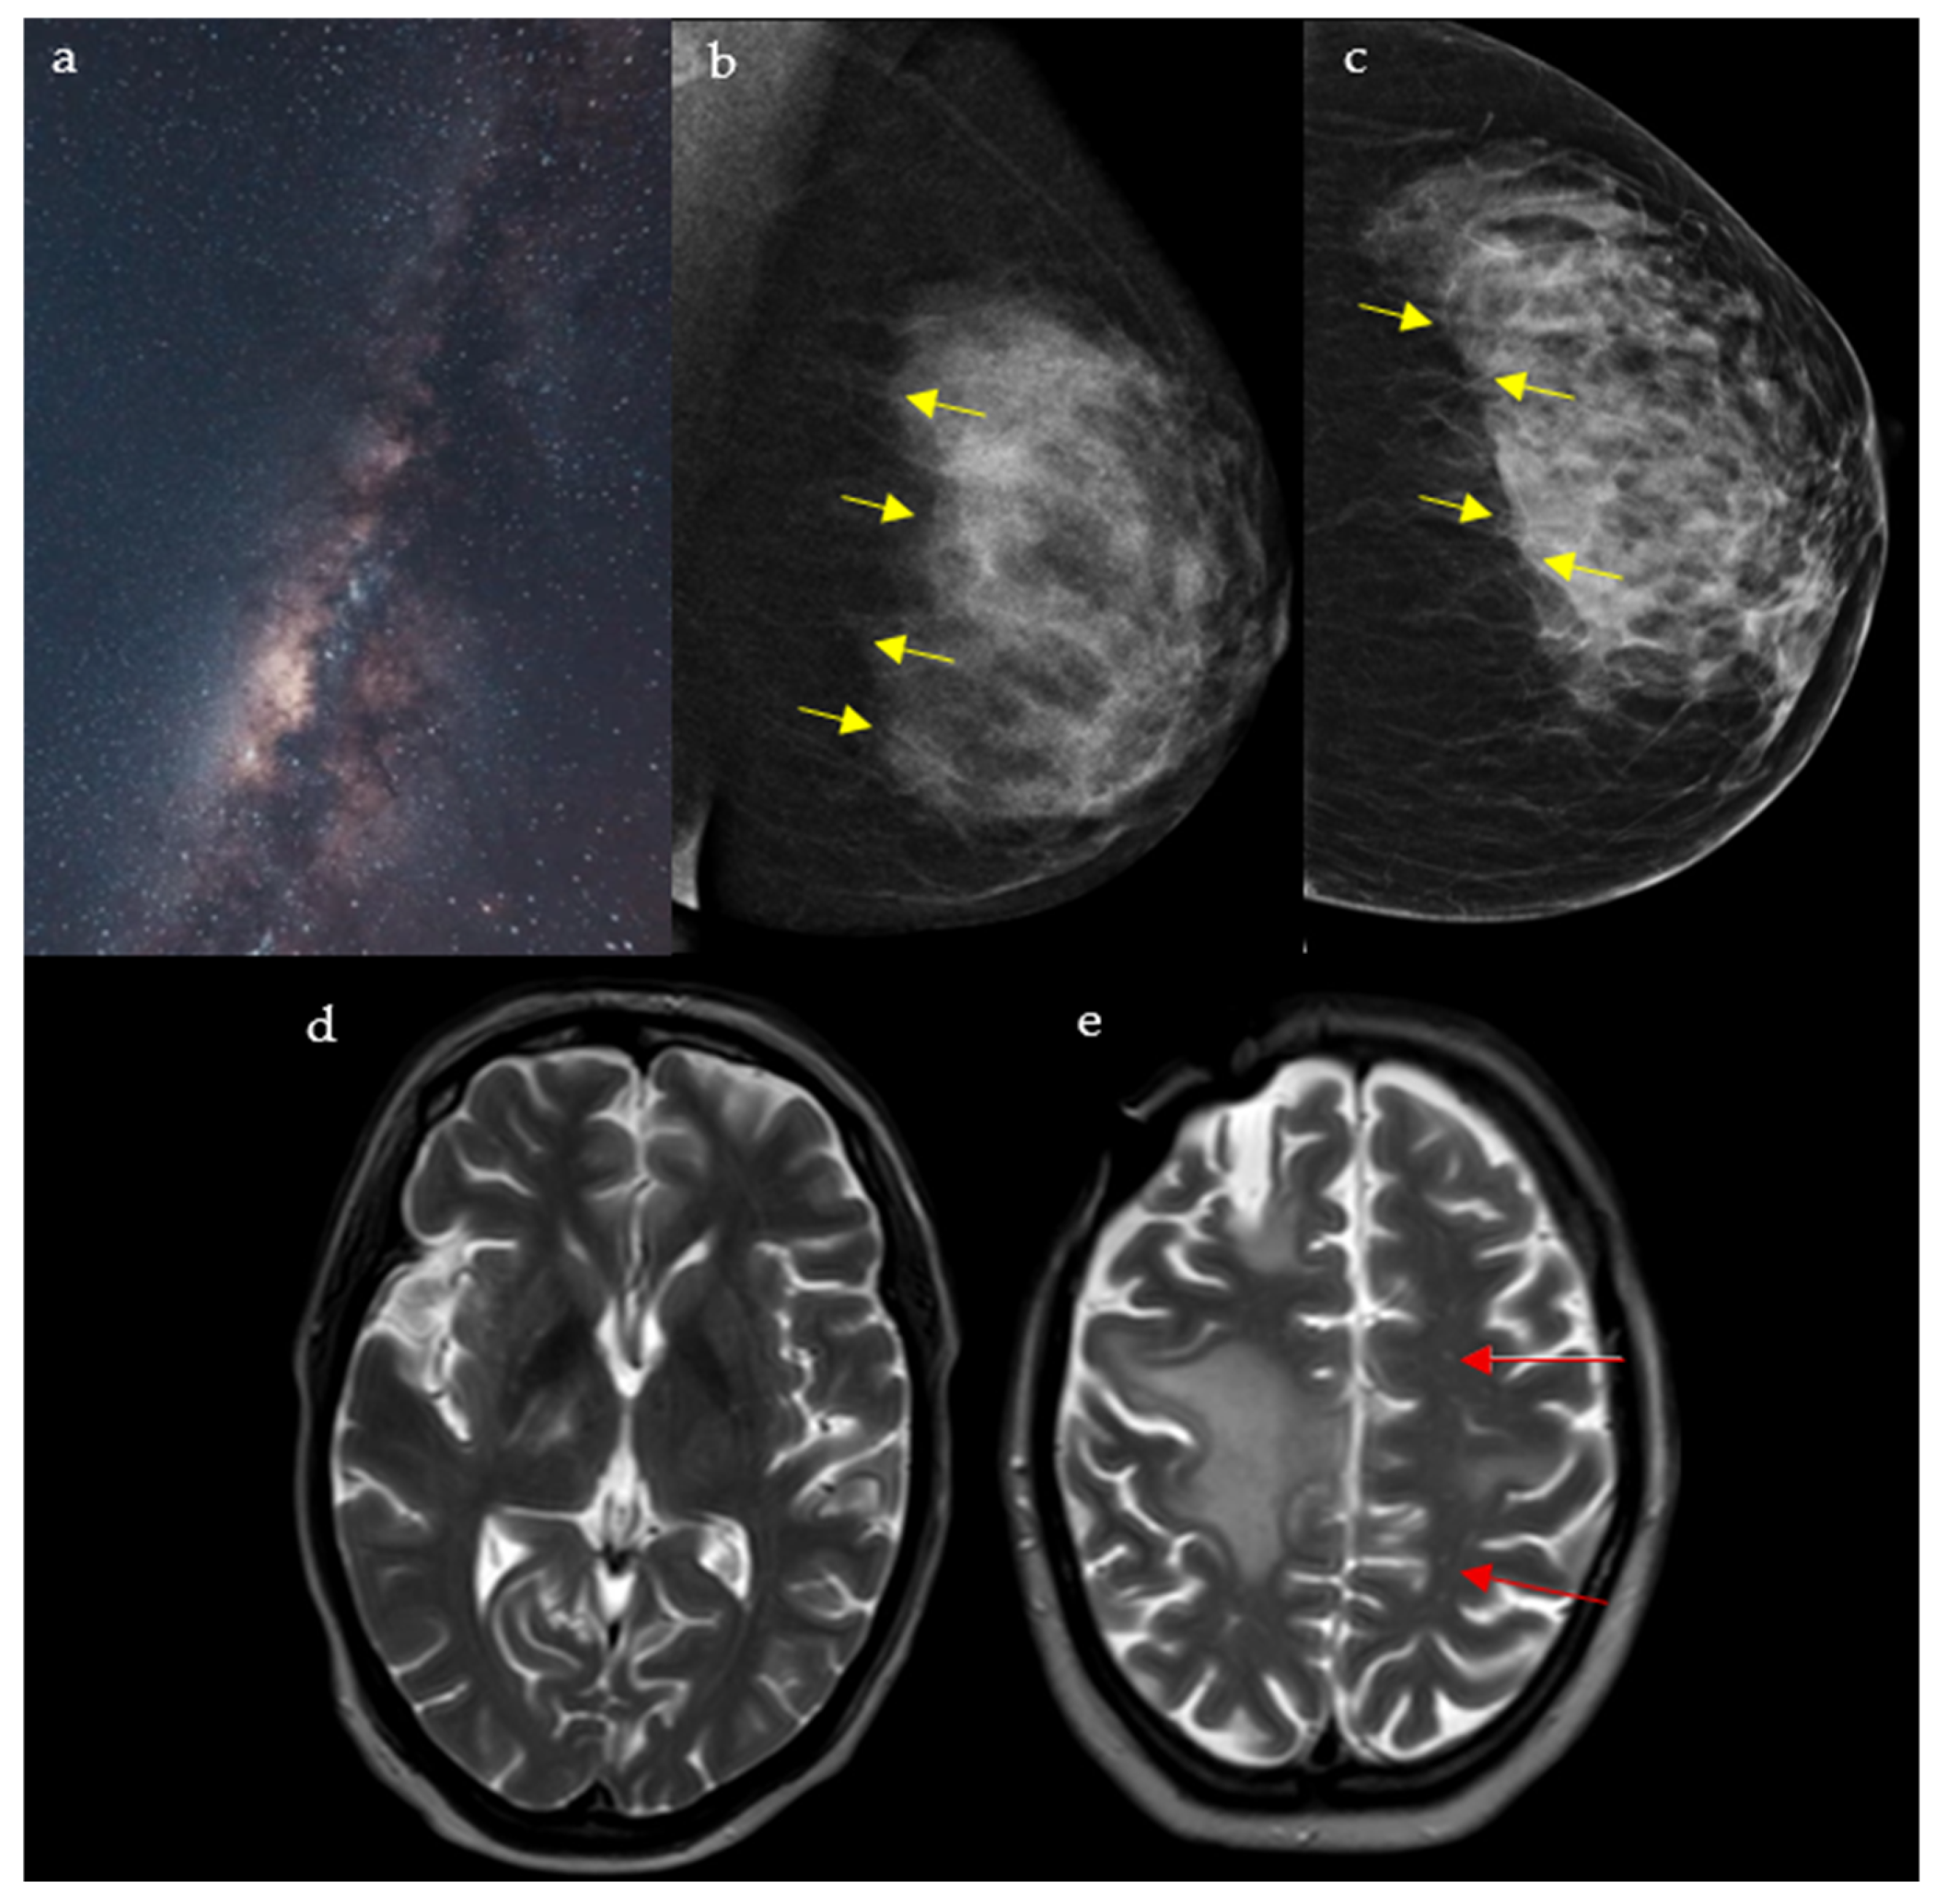

2.5. Milky Way Sign

2.5.1. On Breast Imaging

2.5.2. In Neuroimaging